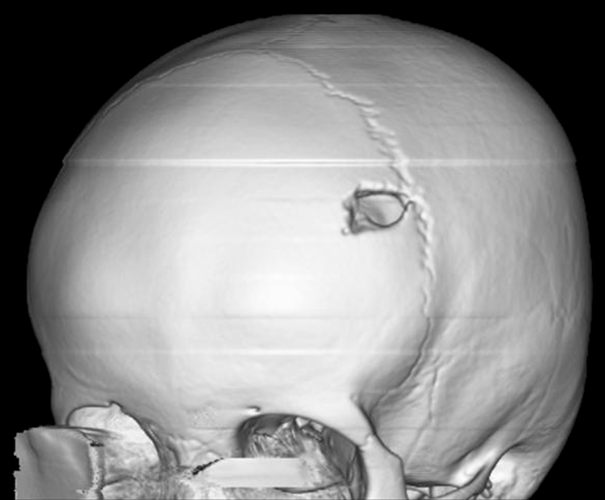

Рисунок 1. 3D-реконструкция костей черепа с солитарной эозинофильной гранулемой

https://radiopaedia.org/cases/eosinophilic-granuloma-skull